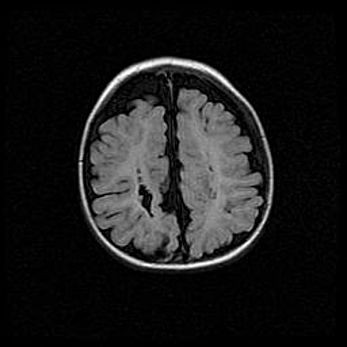

Церебральная ишемия II.

Возраст: 5 дней

Вес: 3400 г

Пол: женский

Окружность головы: 35 см

Срок гестации: 39 недель

Церебральная ишемия – это заболевание, характеризующееся недостаточностью (гипоксией) либо полным прекращением (аноксией) снабжения мозга кислородом по причине закупорки одного или нескольких сосудов. Это приводит к  что метаболическим расстройствам различной степени тяжести в тканях головного мозга, развитию коагуляционных некрозов и гибели нейронов.